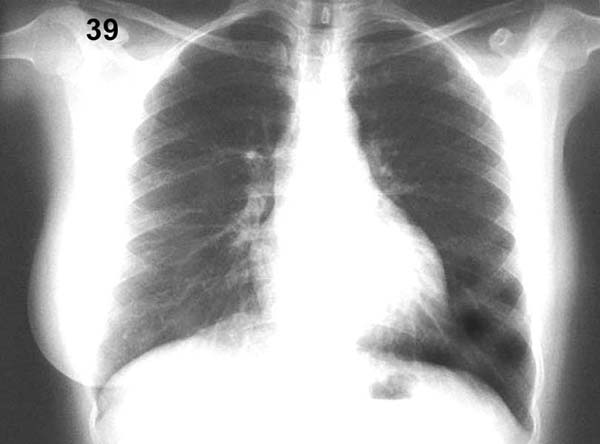

Esquema 39 Comentario placa 39 La base del pulmón izquierdo aparece mas traslúcida, pero ello no se debe a patología pulmonar sino que a la ausencia de mama en ese lado por una mastectomía. No debe olvidarse que las paredes del tórax contribuyen a la imagen radiográfica global. |